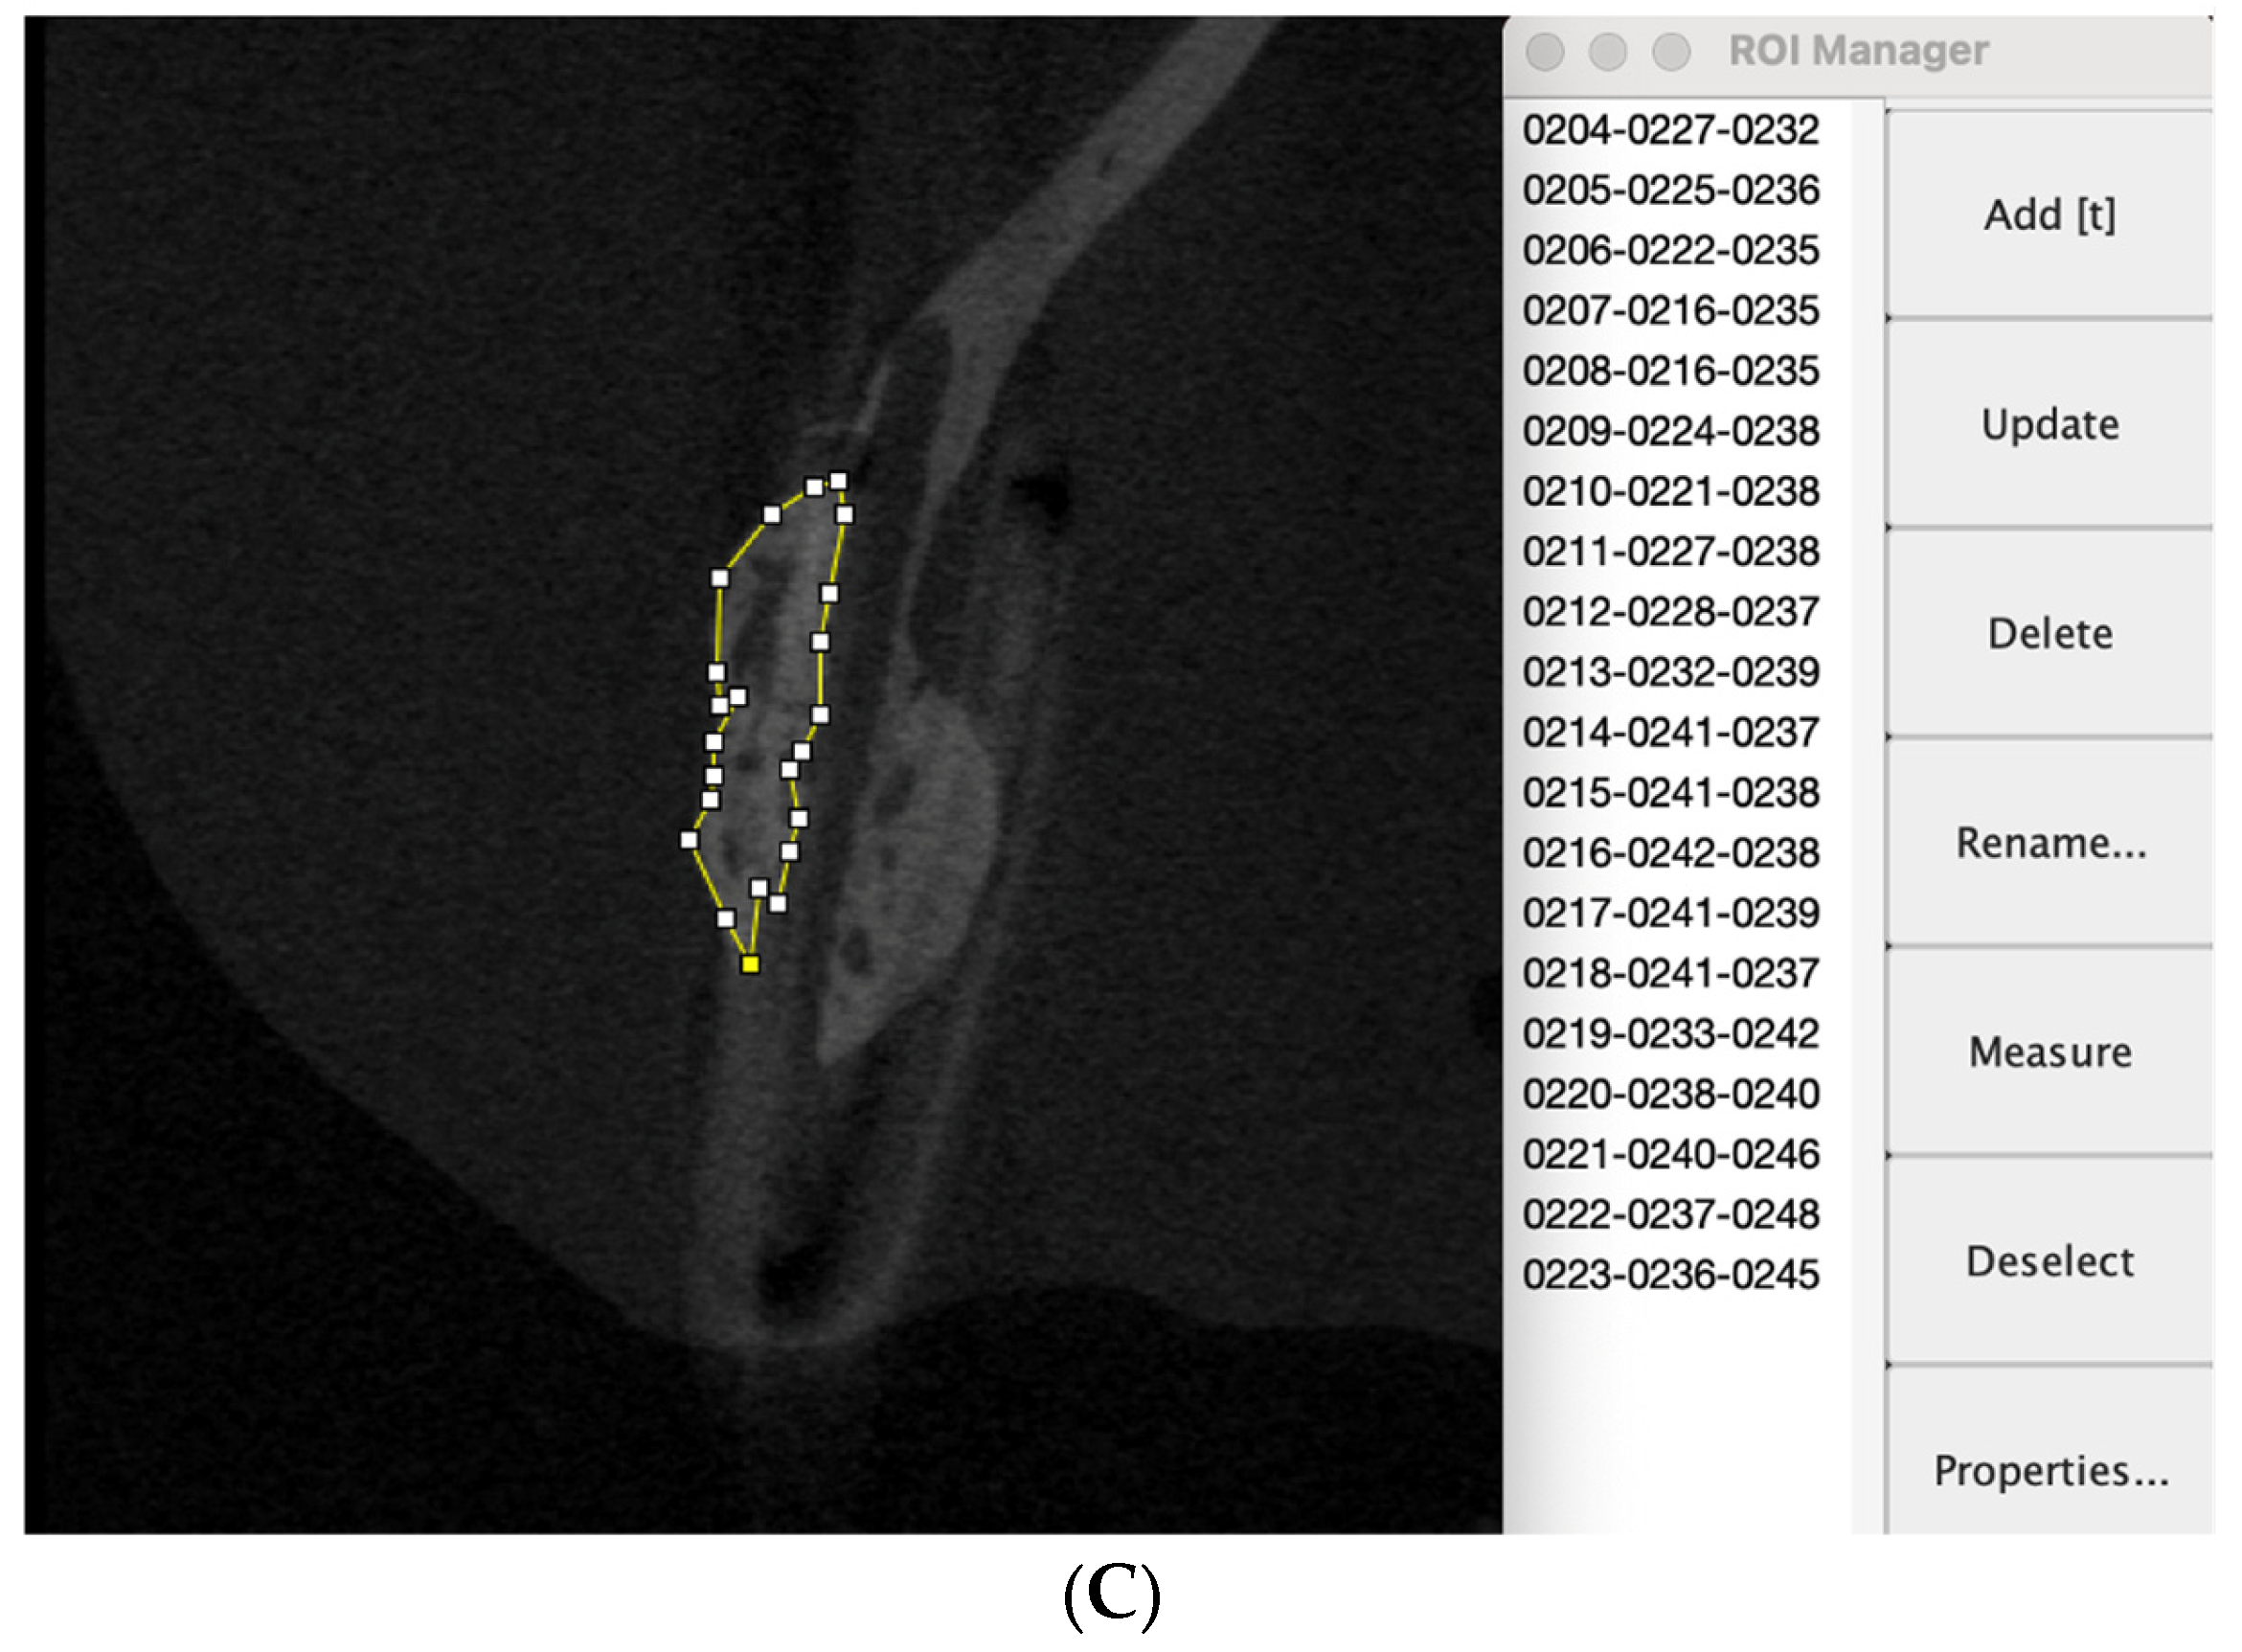

2.3. Assessment of New Bone Formation Using Micro-CT

3.1. Volume of New Bone Formed Outside Sheet